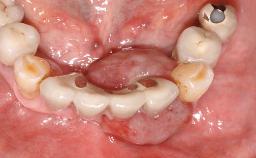

Peri-implantitis Treated with Access-Flap Surgery

A 27-year-old male was referred to the periodontist for assessment and management of implant site 41. The implant had been placed nine years previously and restored with a screw-retained single crown. The patient was a cigarette smoker in good general health. He reported he had reduced his smoking habit from 25 cigarettes per day to 15 cigarettes per day in the previous six months. On examination, there was calculus and plaque present at the lower anterior teeth and at implant site 41. Localized attachment loss was observed at teeth 32 and 42, with 2–3 mm of gingival recession. At implant site 41, there were 8–9 mm probing depths with suppuration and bleeding on probing.